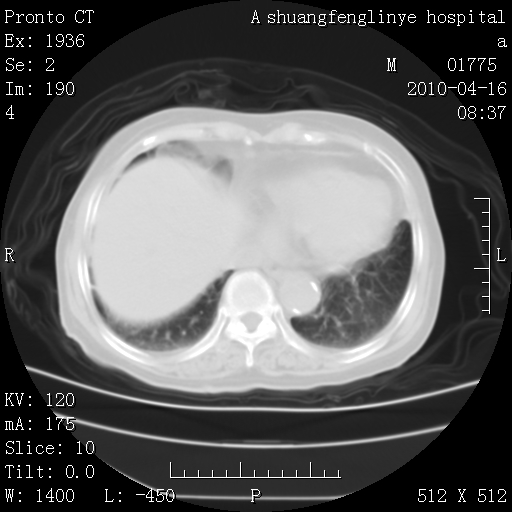

标题: CT25784:咳痰、请会诊!结核?

陈旧性结核,胃腔扩大,脾脏受压后移

考虑左肺上叶增殖灶、纤维灶。

慢支肺气肿,左上陈旧性结核,主动脉冠脉钙化

1)左肺上叶结核(纤维、增殖病灶)。2)冠状动脉及主动脉钙化。

1)左肺上叶结核(纤维、增殖病灶)。2)冠状动脉及主动脉钙化。肺动脉高压